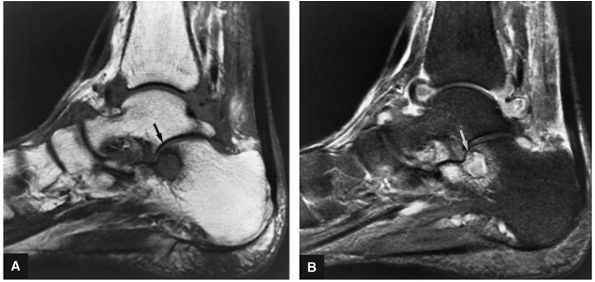

Stage IIB: Incomplete separation of the fragment (Fig. 5.97)

FIGURE 5.97 ● Stage II (IIB) OLT with a shallow and wafer-shaped fragment and incomplete separation from the lateral talar dome. (A) Coronal T1-weighted image. (B) Coronal FS PD FSE image. (C) Sagittal FS PD FSE image. (D) A nondisplaced partial fracture shown in a color graphic corresponding to either a communication with the talar dome or an open articular surface lesion with incomplete separation of the fragment. Subchondral cystic lesions are associated with extension of a fracture to the talar chondral surface.

FIGURE 5.98 ● Stage III OLT with fragment adherent to granulation tissue but separated from the overlying chondral surface, (A) Coronal section color graphic. (B) Coronal T1-weighted image. (C) Coronal FS PD FSE image.

FIGURE 5.99 ● Nondisplaced fragment in a stage III OLT with intermediate-signal-intensity granulation tissue at the fragment—talus interface. (A) Sagittal T1-weighted image. (B) Sagittal FS PD FSE image. (C) Color graphic with superior view of talus.